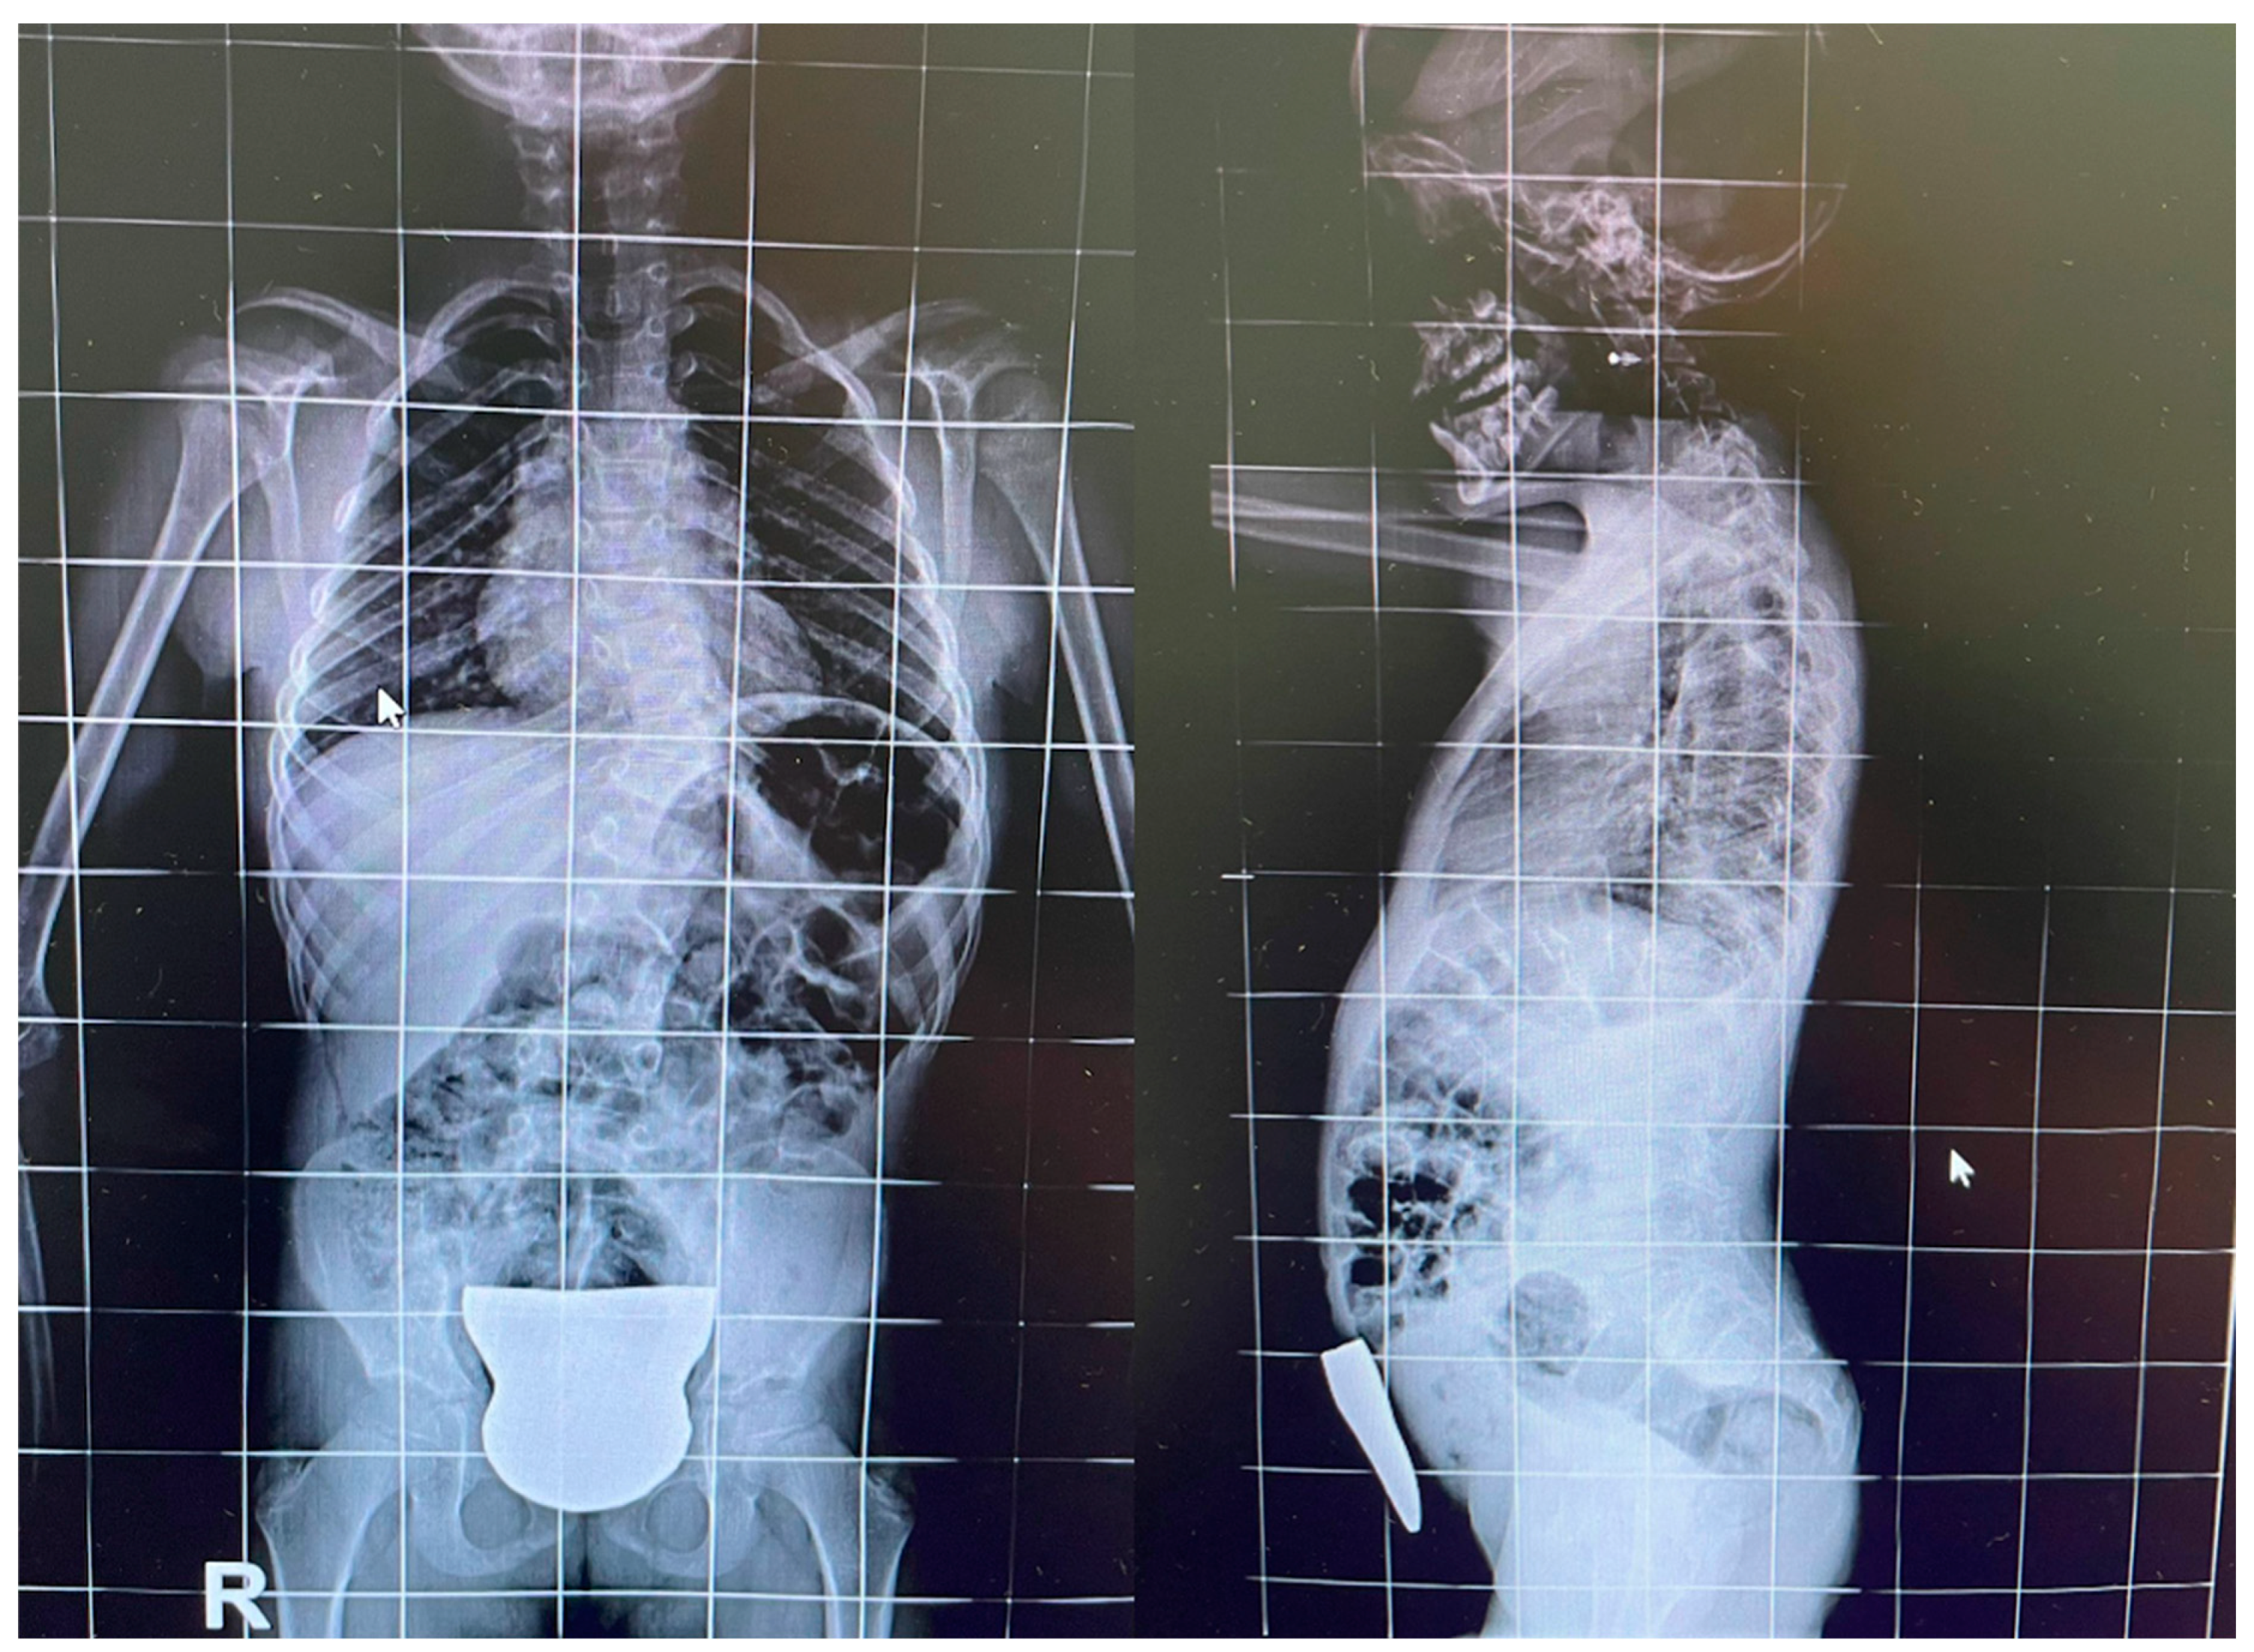

2. Case Report